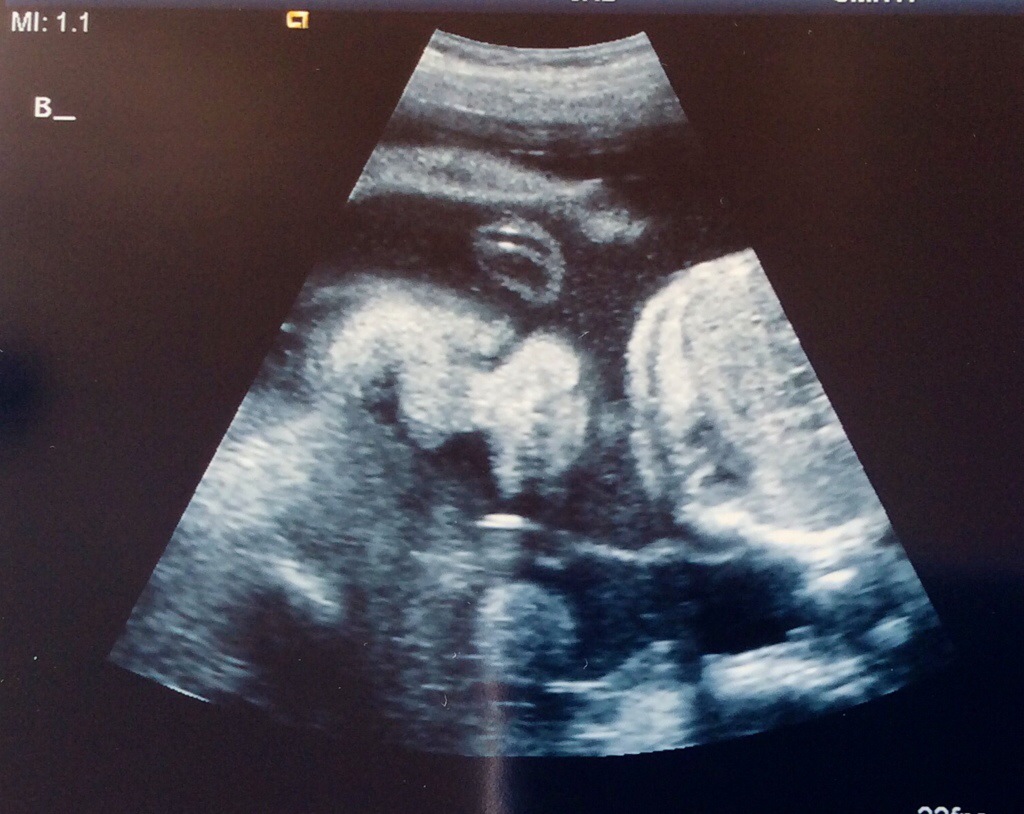

Monday we had our fetal echo and it looks like both babies hearts are just fine. Sigh of relief! Baby A still has her small calcification, but the radiologist was not concerned at all and said not to worry. We also had another growth check at this same ultrasound appointment. Baby A is estimated to be 1 lb 14 oz and Baby B is estimated to be 2 lbs. Baby A is in the 67th percentile and Baby B is in the 83rd percentile. They are growing and we couldn’t be happier!

Baby B Frontal View #1